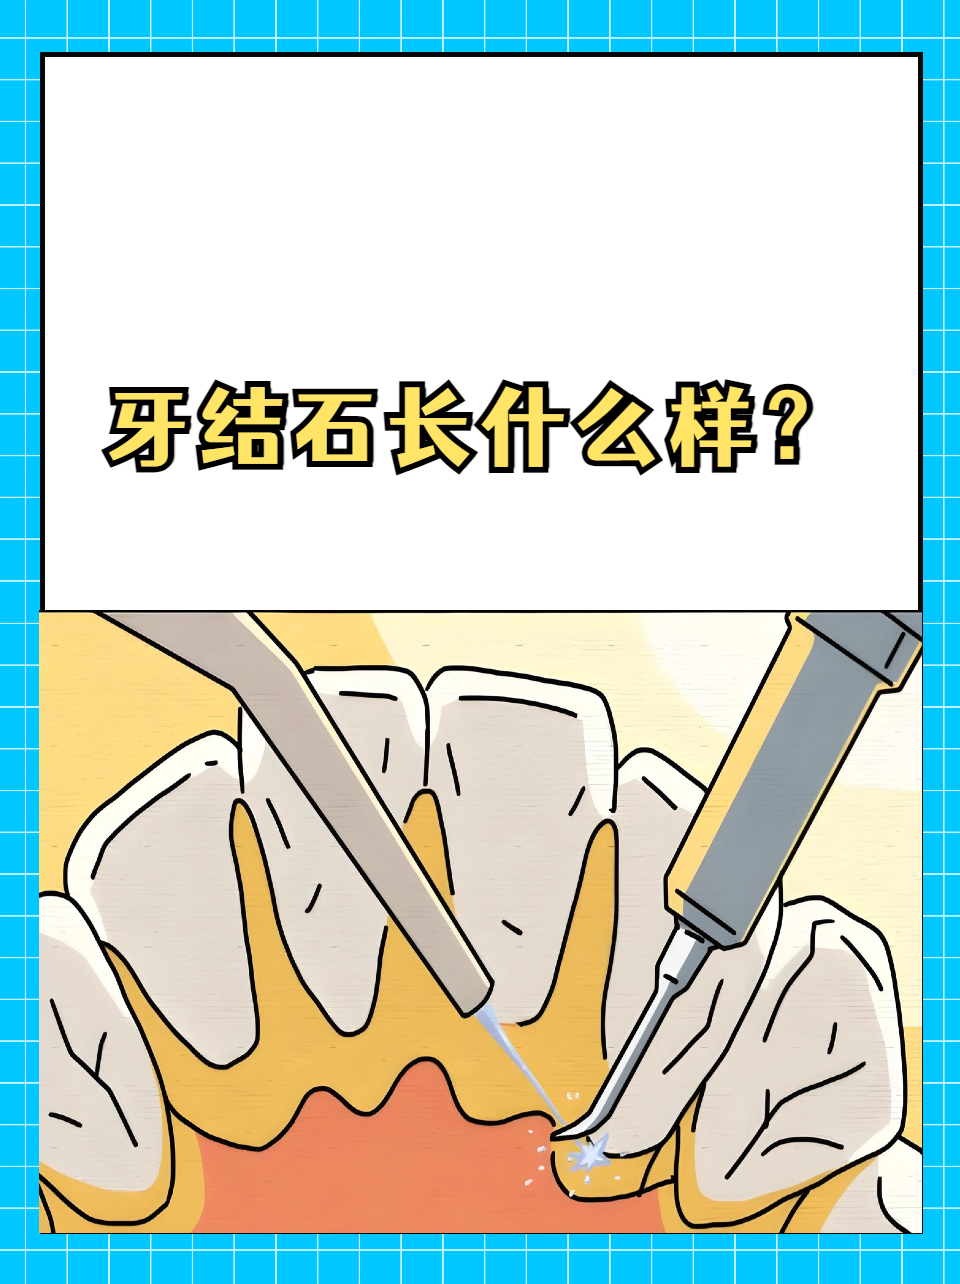

解压动画:我滴妈!这牙结石这么多!

口腔头号杀手牙结石

牙结石如何一步步"攻占"牙齿 牙结石由牙菌斑钙化沉积形成,是口腔健康